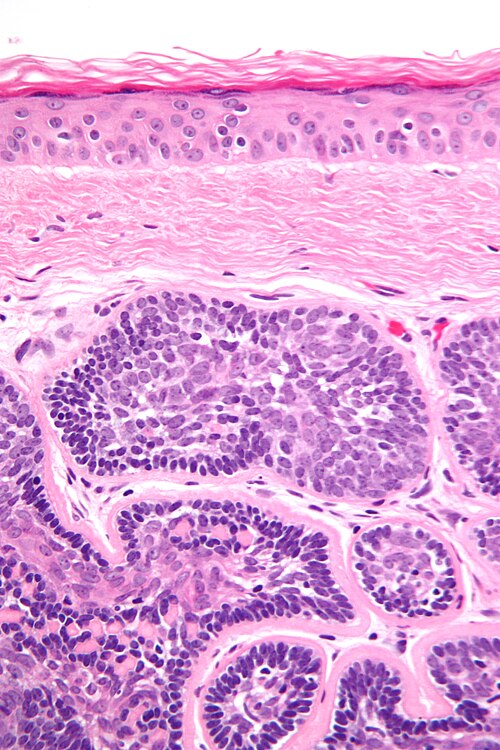

53 year old man, scalp lesion

Site

skin

Intermediate magnification. H&E stain.